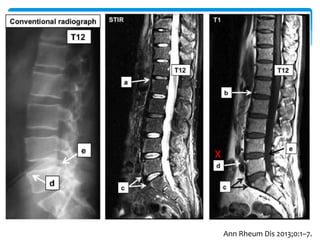

Spine

T1 white, STIR dark

Bone marrow

edema, STIR white,

T1 dark

Romanus lesion

Active lesion

Chronic lesion

SPARCC MRI spinal score (0–108)

Arthritis Rheum. 2005 Aug 15;53(4):502-9.

Ann Rheum Dis 2013;72:967–973

Ann Rheum Dis 2013;0:1–7.